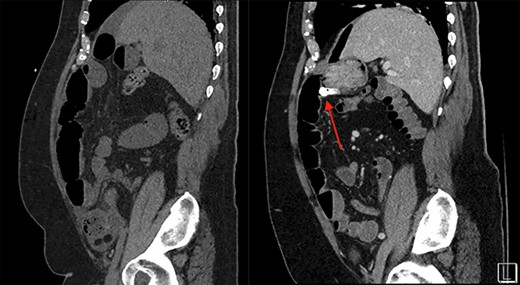

The next week, unbeknownst to his Gastroenterologist about his recent small bowel obstruction admission, he then proceeded with a capsule endoscopy study to assess for other causes of his anemia. He tolerated the pre-operative bowel preparation without issues. After swallowing the capsule, he subsequently had bloody bowel movements. He then went to the ER and found to have a hemoglobin of 7.1, which was decreased from his prior week’s hospitalization, 8.4. A CT angiography (CTA) abdomen and pelvis was then performed that showed a 4 × 6 × 4.1 cm mass in the right upper quadrant with the capsule endoscopy at the level of the mass (Figs 1 and 2). The images from the capsule were unremarkable. On review of his imaging with radiology, it appeared that this mass was not apparent without IV contrast on his previous CT scan a week prior. In addition, a prior CT abdomen pelvis with IV contrast 10 months ago was negative for a small bowel mass. A repeat abdominal and pelvis CT with oral and IV contrast was done for confirmation. This re-demonstrated the 6 cm mass with the capsule stuck proximal to it; therefore, we performed a diagnostic laparoscopy.

Surgery revealed a small bowel tumor in the jejunum (Figs 3 and 4), which was resected and intestines re-anastomosed. The capsule was not identified within the lumen of the resected segment and had traveled through the obstructed segment distally. He had an unremarkable recovery and sequential X-rays demonstrated passage of the capsule. The pathology revealed metastatic renal cell carcinoma with intraluminal mucosal ulceration, 0/6 lymph nodes positive. He did well post-operatively and was referred back to his oncologist for further evaluation of his cancer.